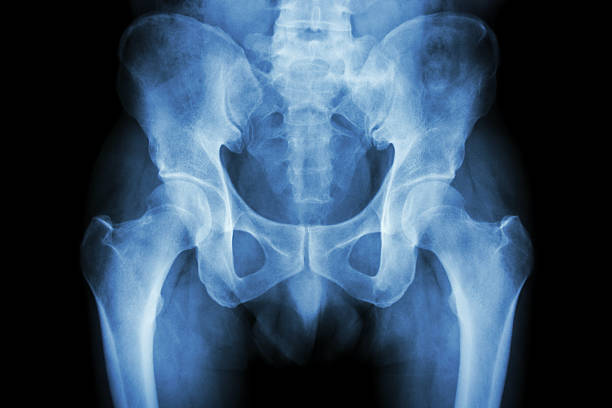

고관절 충돌 증후군

고관절 충돌 증후군은 엉덩이 통증의 주요한 원인 중 하나입니다. 이 질환은 골반 뼈와 대퇴골 사이에서 발생하는 충돌에 의해 2 관절 사이의 연골이 손상되는 질환입니다. 고관절의 구조적인 문제나 잘못된 자세, 과도한 스트레칭 등으로 발생할 수 있습니다.